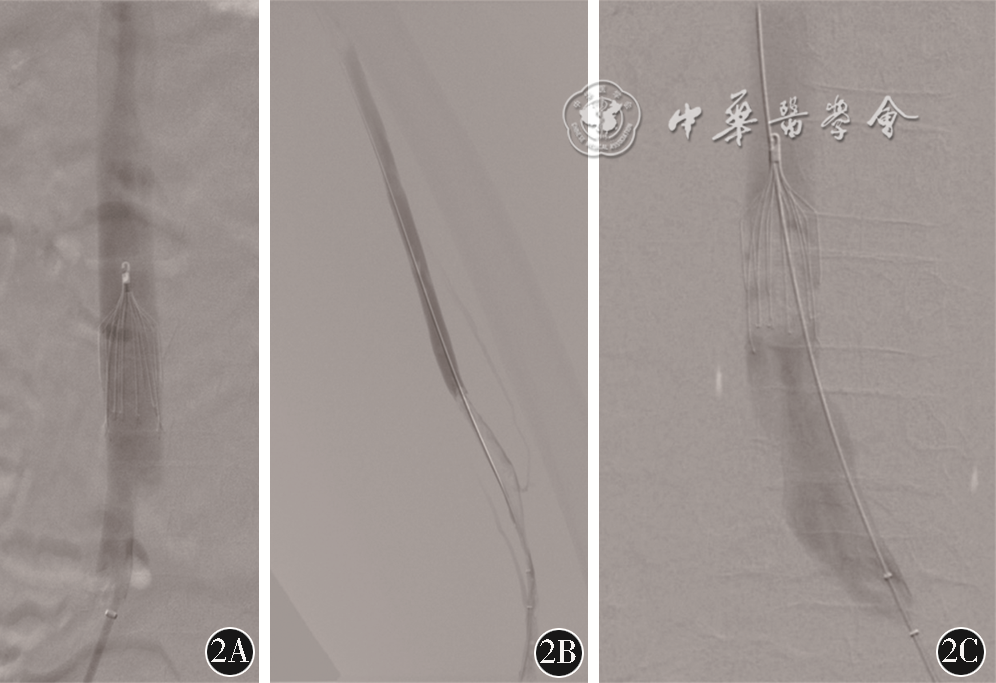

患者3 女性,13岁,BMI 28 kg/m2。因“左下肢肿痛1 d”于2021年8月24日急诊入院。患儿1 d前患儿出现左下肢肿胀伴疼痛,无发热、喘憋。既往患儿鞍区肿瘤,1年前、5个月前分别行2次手术切除,病理学检查示混合生殖细胞瘤,2周前完成第4次化疗。术后规律口服醋酸去氨加压素(弥凝)、氢化可的松、左甲状腺素钠。患儿左眼无视力,尿量正常,近期卧床、进食水较少。体格检查:心率130次/分,血压105/ 65 mmHg,指氧监测:90%(未吸氧下),100%(吸氧,2 L/min)。双肺呼吸音粗,左下肢轻度增粗。实验室检查:D-二聚体 4.95 mg/L FEU,血红蛋白 95 g/L,白细胞 8.47×109/L。下肢静脉超声示左侧股总及大隐静脉血栓形成。CTPA见左下、右上、右下肺动脉栓塞,右心左心比1.01(图3A、3B)。

注:CDPA为CT肺动脉造影;CDT为导管溶栓术;PMT为药物机械血栓清除

遂于2021年8月24日行肺动脉血栓清除+下腔静脉滤器置入术(图3C、3D)。经右侧股静脉入路,DSA见左侧髂静脉血栓延续至下腔静脉,近端位于肾静脉水平;下腔静脉肾上段放置下腔静脉滤器(图3E);左侧肺动脉主干经猪尾导管予尿激酶5万U行CDT治疗,右侧肺动脉主干予尿激酶15万U行AngioJet PMT,AngioJet治疗期间出现一过性血压下降,收缩压<90 mmHg,3 min后缓解,指氧监测平稳;复造影见右侧肺动脉血流未见明显改善;下腔静脉肾下段尝试AngioJet PMT,血压下降明显,收缩压<70 mmHg,5 min后自行缓解;中止手术。术后入ICU,予普通肝素钠静脉泵入抗凝治疗,维持部分凝血活酶时间50~70 s。术后1周患儿D-二聚体呈一过性升高后稳步下降的典型溶栓曲线(9.9 mg/L ->8.11 mg/L ->3.33 mg/L ->1.48 mg/L ->0.98 mg/L),复查CTPA和CT静脉造影示肺动脉及下腔静脉血栓未见明显变化。患儿术后因垂体疾病尿量控制困难,2021年8月30日出现急性心功能不全、双下肺不张和坠积性肺炎,于2021年9月6日死亡。